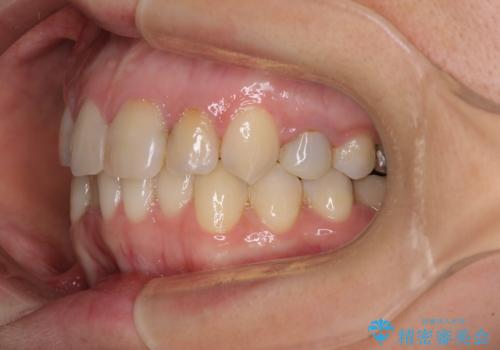

【モニター】前歯のデコボコと奥歯の虫歯 インビザライン治療と奥歯のセラミック治療

- 前歯のデコボコと奥歯の虫歯を気にして来院された患者様です。

主に下顎歯列全体の後方移動とIPR(歯と歯の間を削る)によってデコボコが解消するように設計し、インビザラインにより治療を行うこととしました。

矯正治療後半に下顎左右奥歯をセラミッククラウンにて補綴し、その後インビザラインによる歯列の仕上げを行うこととしました。

下顎前歯の叢生が速やかに改善されたため、1年3か月で治療を終えることができました。

下顎前歯は後戻りを起こしやすいため、舌側を細いワイヤーで固定することで後戻り対策を行っています。